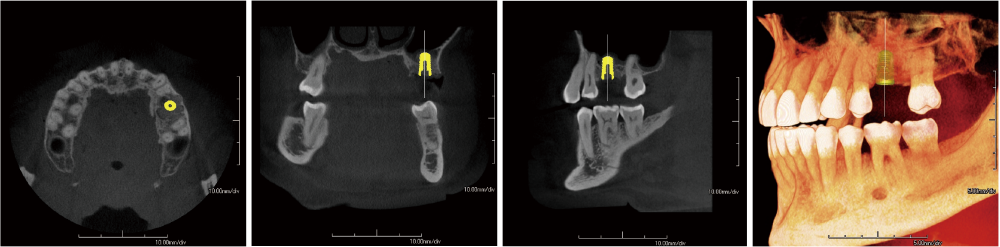

With dentists from various fields of expertise as advisors, we have carefully selected FOVs that are commonly used in clinical practice. In addition to the 3D analysis function for image detail sizes of 5x5cm, 10x10cm, 15x10cm and 15x16cm, the device features “True” and “Reconstructed” panoramic modes. With one of the largest FOVs on the market, the PreXion3D EXPLORER helps to develop the best therapy options, particularly in oral and maxillofacial surgery, airway analysis and orthodontics, as well as ear, nose and throat medicine. The use of a large 25.4x31.7cm FPD enables 15x16cm FOV scanning in one rotation.

The precise and high-resolution display of hard and soft tissue enables outstanding diagnostics and planning across all areas of modern dentistry and maxillofacial surgery. A large high-definition FPD allows all FOVs scanned in a single rotation without using stitching function.

With many 3D imaging systems on the market today, high-quality images are often accompanied by high radiation exposure. The PreXion3D EXPLORER offers balance of both aspects. The PreXion3D EXPLORER utilizes the industry’s smallest 0.3mm x-ray tube focal spot and voxel sizes from 0.07mm to 0.3mm for all FOV sizes. In addition, by adopting a high X-ray tube voltage of 110kV, pulsed X-ray irradiation, 16bit gray scale, and a newly developed large FPD, it simultaneously achieves high-definition image quality for a wide range of dental clinical practice and low radiation exposure for patient safety.

The focal spot, also called focus, is the area on the target of the X-ray tube which is struck by the electron stream and emits X-rays. The larger the focal spot’s area, the poorer the detail of the image. The PreXion3D EXPLORER utilizes one of the smallest size focal spots in the industry at 0.3mm for all FOVs.

A combination of the words “volumetric” and “pixel”, a voxel is a three-dimensional volume element shaped like an isometric cube. The PreXion3D EXPLORER offers powerful imaging software with voxel sizes ranging from 0.07 to 0.3mm in order to maintain image quality.